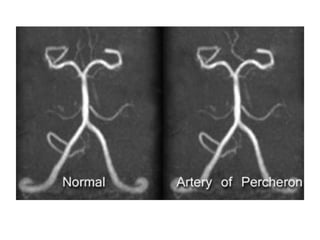

-Artery of Percheron is a variant where there is a

dominant thalamic perforator supplying the

ventromedial thalami bilaterally and the rostral

midbrain arising from a P1 PCA segment , an artery

of Percheron infarct will result in bilateral

ventromedial thalamic infarction with (pattern 1) or

without (pattern 2) midbrain infarction (the infarct

may be V-shaped if the midbrain is involved , deep

venous thrombosis may also result in bilateral

thalamic infarcts

DSA of the left vertebral injection , lateral (A) and anteroposterior (B) views

and a coronal CTA image (C) show a large unpaired thalamic perforating

artery (arrows) arising from the proximal P1 segment supplying the

bilateral thalami (i.e. Artery of Percheron)